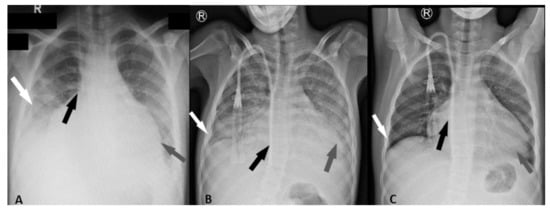

2. Case Presentation